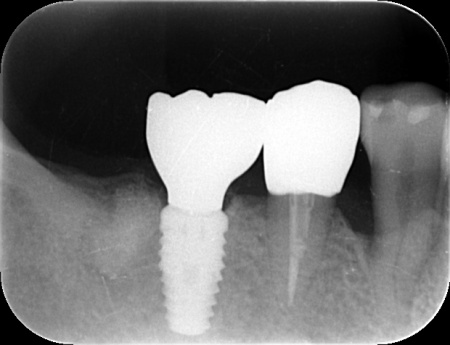

拝見したところ、右下の奥歯(第1大臼歯)に歯根破折が確認でき、これが痛みの原因だと考えられます。

そこで、レントゲン検査などで詳しく確認した結果、ひびは根の深い部分まで達しており、残念ながら歯を温存することは困難です。

患者様は「できるだけ治療期間を短くしたい」と希望されていることから、右下の第1大臼歯は抜歯即時埋入インプラントを提案しました。

抜歯即時埋入インプラントとは、抜歯と同日に人工歯根「インプラント体」を埋め込む方法です。

これにより、通常のインプラントと比べて治療期間を短縮することができます。

抜歯後、感染した組織を慎重に除去し同日にインプラント体を埋入しました。

骨とインプラントが結合するまでの期間は仮歯を装着し、噛み合わせや周囲組織の状態を確認しながら経過を観察しました。

骨とインプラントがしっかりと結合していることを確認したあと、型取りを行い被せ物を作製・装着しています。